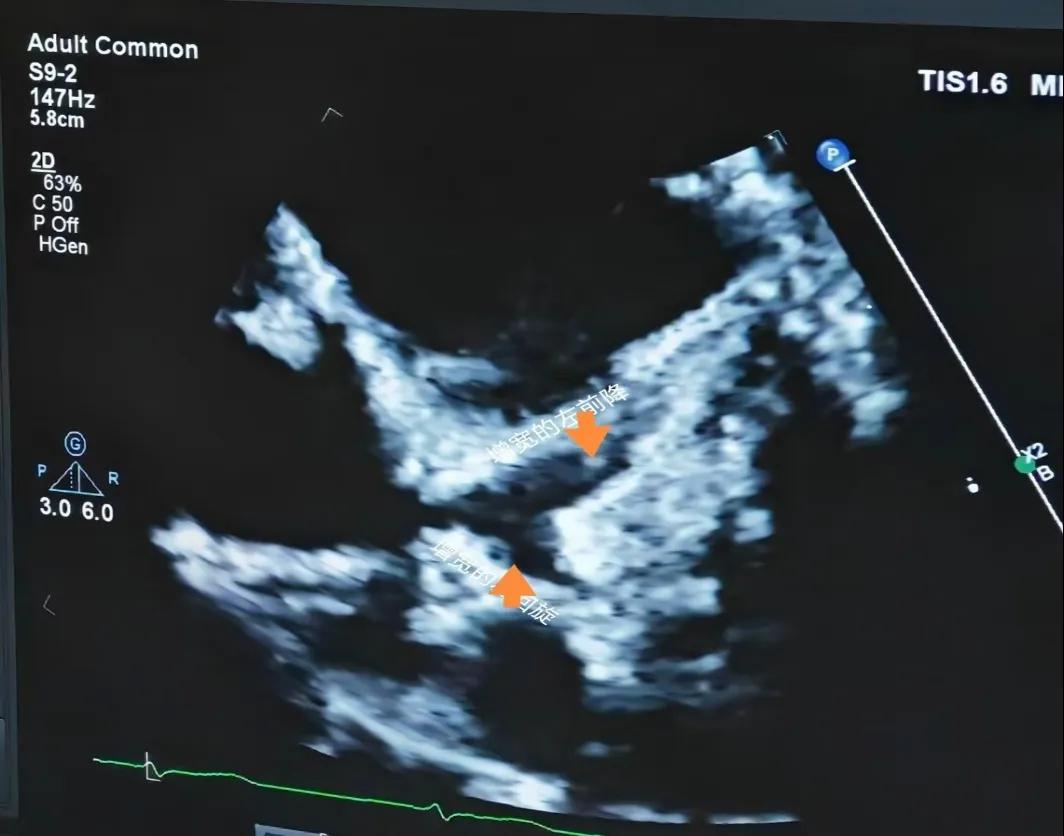

(川崎病患兒:增寬的左前降支和左回旋支)

(川崎病患兒:增寬的右側(cè)冠狀動脈)